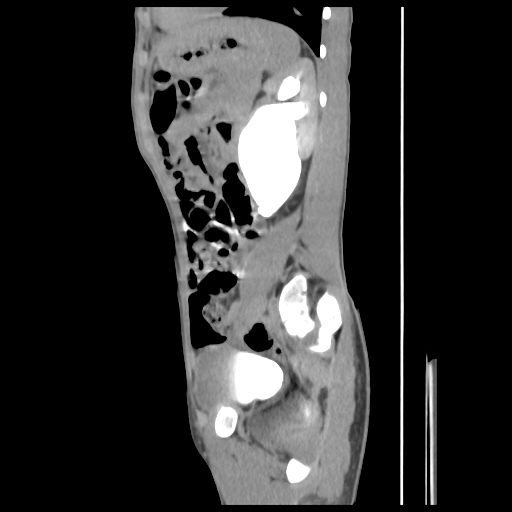

current CT images: